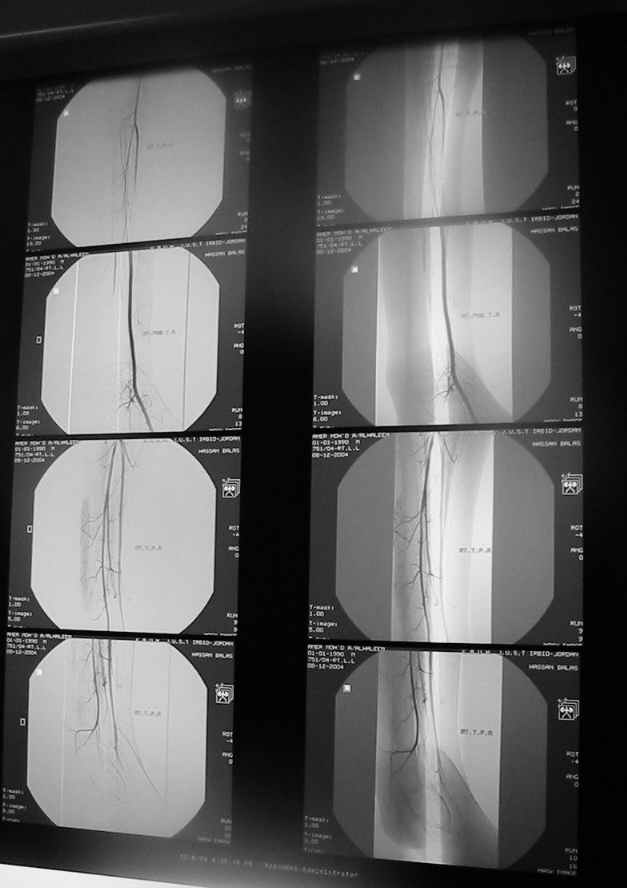

Судя по представленным фото и Рг граммам, у 13 летнего ребенка врождённая гемимелия большеберцовой кости, таранно-пяточный синостоз Из-за отставания в росте большеберцовой кости (остутствует дистальный эпифиз с зоной роста) произошла компенсаторная гиперофия малоберцовой кости, на которую приходится основная нагрузка (спонтанная тибиализация малоберцовой кости). Как результат дисбаланса осевого роста вторично возникла эквино-варусная деформация стопы. Продолжающийся рост ребёнка (до естественного закрытия зон роста) будет приводить к усугублению деформации по приведенным выше причинам.

Своё наблюдение только одно (ребёнка наблюдали и продолжаем наблюдать с рождения) и дважды оперировали: 1 этап выполнили проксимальный тиб/фиб фьюжн вторым этапом медиализация малоберцовой кости с таранно- малоберцовым синостозом и ещё предстоят этапы по удлинению тибиализированной малоберцовой кости.

Поднадкостничную остеотомию большеберцовой кости в средней трети с формированием синостоза с малоберцовой ( активно растущей) костью и второй уровень в области дистального тиб/фиб синдесмоза- достигается баланс роста( средне-медиальный и латеральный отделы) в области измененного голеностопного сустава. Коррекция эквино-варусной деформации стопы в аппарате после чрезкожной сегментарной тенотомии ахилова сухожилия. Дело

кропотливое и длительное.